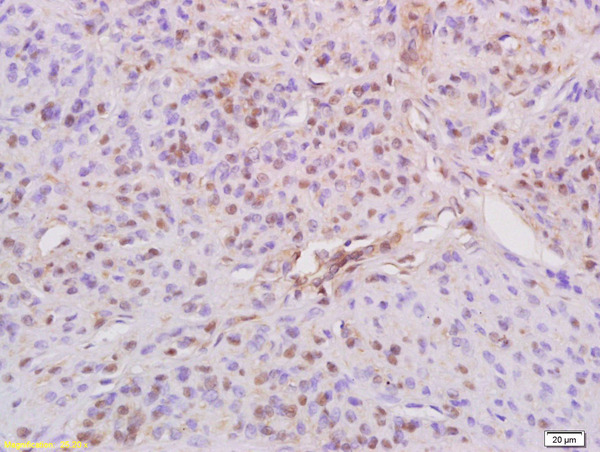

phospho-IRS1 (Ser636 + Ser639) Polyclonal Antibody

• IHC-P

Applications IHC-P, IHC-F, IF, Flow-Cyt, ICC/IF

Specificity This phosphorylation site is homologous to Ser632 + ser635 in Mouse and Rat IRS1. This protein is known to be highly conserved in this sequences region, thus , this antibody may react with IRS2 when phosphorylated at Ser679 + Ser682 in Human , Ser675 + Ser678 in Mouse, and Ser676 +Ser679 in Rat based on homology.

IHC-P WB1:300-5000

Flow-Cyt IHC-P1:200-400